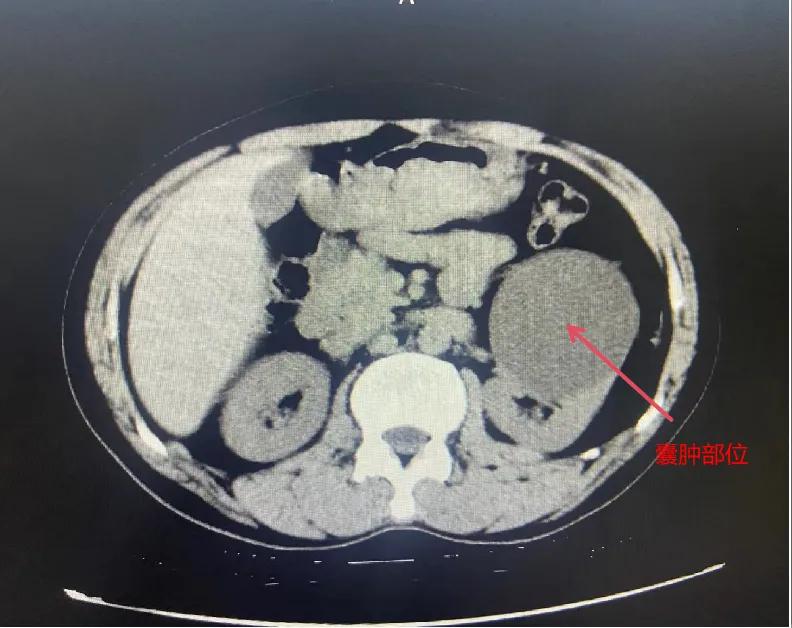

漯河市骨科醫(yī)院泌尿外科開展后腹腔鏡下腎囊腫去頂減壓術(shù)

近日,漯河市骨科醫(yī)院(漯河醫(yī)專二附院、漯河市立醫(yī)院)連續(xù)收治2例腎囊腫患者。泌尿外科主任閆衛(wèi)甫和副主任醫(yī)師王金柱等醫(yī)師團(tuán)隊(duì)經(jīng)討論研究后,決定為患者采取后腹腔鏡下腎囊腫去頂減壓術(shù),經(jīng)過手術(shù)室、麻醉科等科室大力配合成功完成手術(shù)。

閆衛(wèi)甫表示,后腹腔鏡技術(shù)是一種微創(chuàng)外科手術(shù)方法,它通過在后腹腔(即腹膜后的空間)建立一個(gè)手術(shù)空間,利用腹腔鏡器械進(jìn)行手術(shù)操作。這種技術(shù)特別適用于泌尿系統(tǒng)等后腹腔臟器的手術(shù)。與傳統(tǒng)手術(shù)相比具有創(chuàng)傷小、恢復(fù)快、并發(fā)癥少、視野清晰等優(yōu)點(diǎn)。與前腹腔鏡相比則具有對(duì)腹腔臟器干擾較少的優(yōu)點(diǎn)。目前,后腹腔鏡手術(shù)主要用于腎囊腫去頂減壓術(shù)、腎上腺腫瘤切除、早期腎癌根治術(shù)、腎腫瘤剜除術(shù)等。

腎囊腫是一種常見的腎臟良性疾病,其發(fā)病率逐年增加。近年來隨著腹腔鏡技術(shù)的迅速發(fā)展,后腹腔鏡下腎囊腫去頂減壓術(shù)成為治療腎囊腫的主要方法。該手術(shù)具有創(chuàng)傷小,手術(shù)時(shí)間短,術(shù)中出血少,術(shù)后康復(fù)快,出院時(shí)間短等優(yōu)點(diǎn),并且術(shù)后復(fù)發(fā)率低,被認(rèn)為是治療腎囊腫的理想術(shù)式。(盧 闖 聶方方 劉 旭 袁錦鈺)